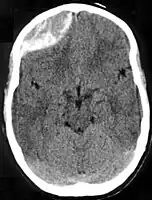

Nontraumatic epidural hematoma in a young woman. The grey area in the top left is organizing hematoma, causing midline shift and compression of the ventricle.

Non-contrast CT scan of a traumatic acute hematoma in the left fronto-temporal area.